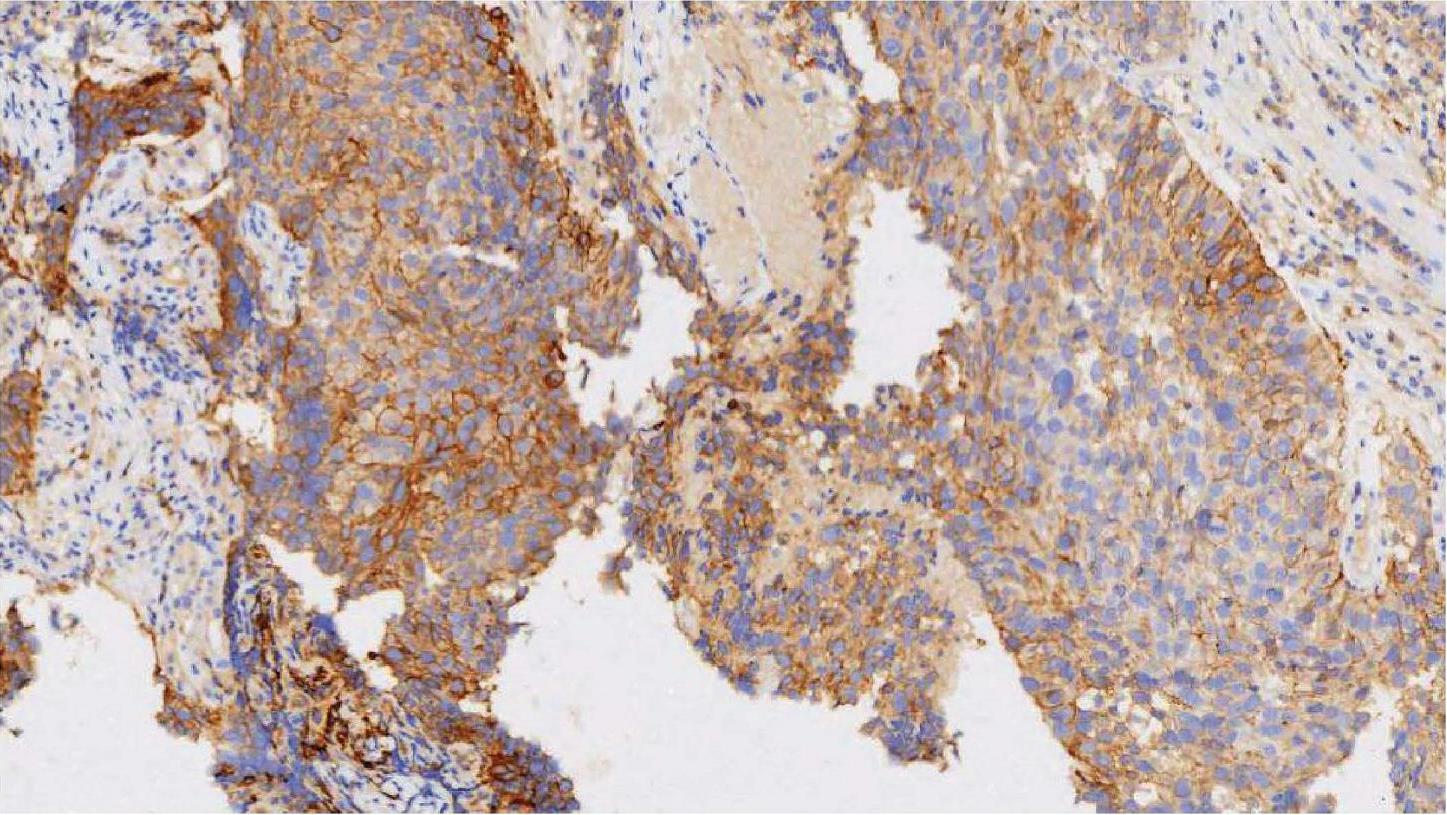

22C3克隆号是国内首个获批的PD-1/PD-L1免疫检测点的伴随诊断试剂。其检测方法固定,检测程序由厂家单独安装,整个检测流程简单高效,只需要熟练操作Dako Autostainer Link 48设备就可胜任检测工作;其自带有批间阴性和阳性对照片,检测结果可重复性高,定位在细胞膜上。PD-L1表达结果以TPS(任何强度部分或完全膜染色的肿瘤细胞占标本中所有肿瘤细胞的百分比)计算;若TPS<1%,诊断为阴性表达;TPS 1%~49%为低表达,TPS≥50%为高表达。图2-3所示为NSCLC PD-L1 (22C3)免疫组织化学染色图,TPS为0;图2-4所示为NSCLC PD-L1 (22C3)免疫组织化学染色图,TPS 1%~49%;图2-5所示为NSCLC PD-L1 (22C3)免疫组织化学染色图,TPS≥50%。

图2-5 NSCLC PD-L1 (22C3)免疫组织化学染色图(×100),TPS≥50% [5]